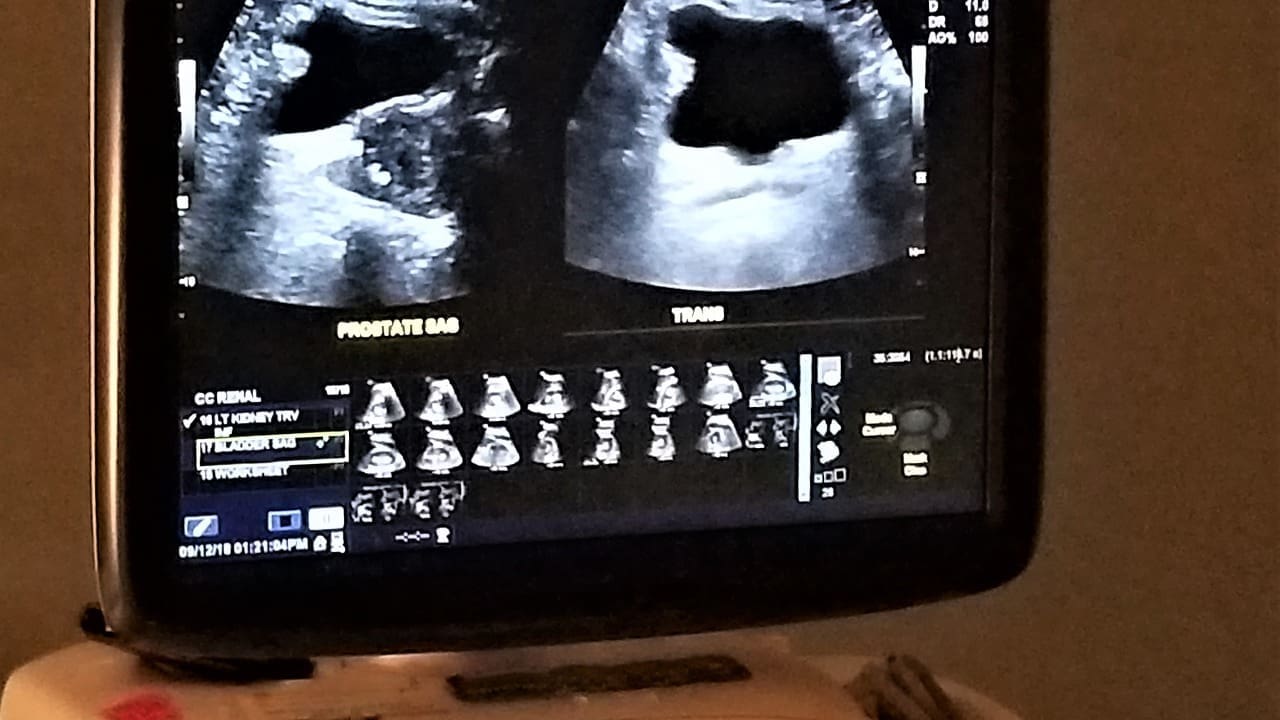

Diagnosing Ectatic Aorta US: Ultrasound Evaluation Techniques

Ultrasound is a key tool for checking the aorta because it’s safe and works well. It helps us see how big the aorta is and if there are any problems like aneurysms. This tool gives us important information about the aorta’s health.

Ultrasound Imaging Protocol for Aortic Assessment

To get a good look at the aorta, we follow a detailed plan. We take many pictures and measurements. First, we look at the aorta from the side, then from the front for more details.

Measurement Techniques and Accuracy

Getting the aorta’s size right is very important. We use a specific way to measure, like measuring from the inside to the inside. This makes sure our measurements are right and can be trusted.